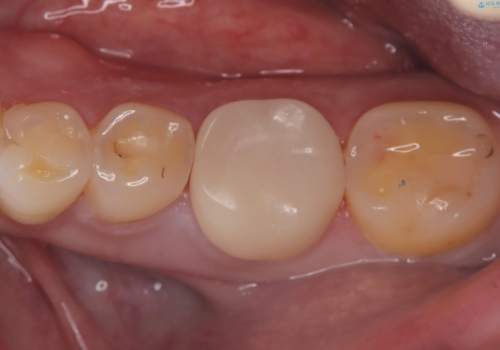

咬合力によるヒビの部分に生じる歪みを軽減するため、クラウンを被せました。

咬合力によるヒビの部分に生じる歪みを軽減するため、ヒビを追えるところまで切削しCR裏層・支台歯形成を行い、一度仮歯に置き換え症状の緩和を確認し、CAD/CAM冠を装着しました。